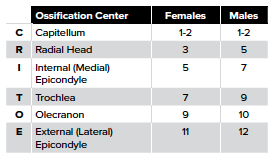

4. Identify ossification centers

There are 6 secondary ossification centers in the elbow. They ossify in a sex- and age-dependent predictable order. CRITOE is a mnemonic for the sequence of ossification center appearance. (Table 1 and Fig 6)

The medial epicondyle fuses to the shaft of the humerus at 13 years for females and 15 years for males. The growth plates are vulnerable to traction or shearing forces which result in fracture and/or apophyseal injuries. Displaced epicondyle fractures can be missed if the normal pattern of ossification development is not recognized.7